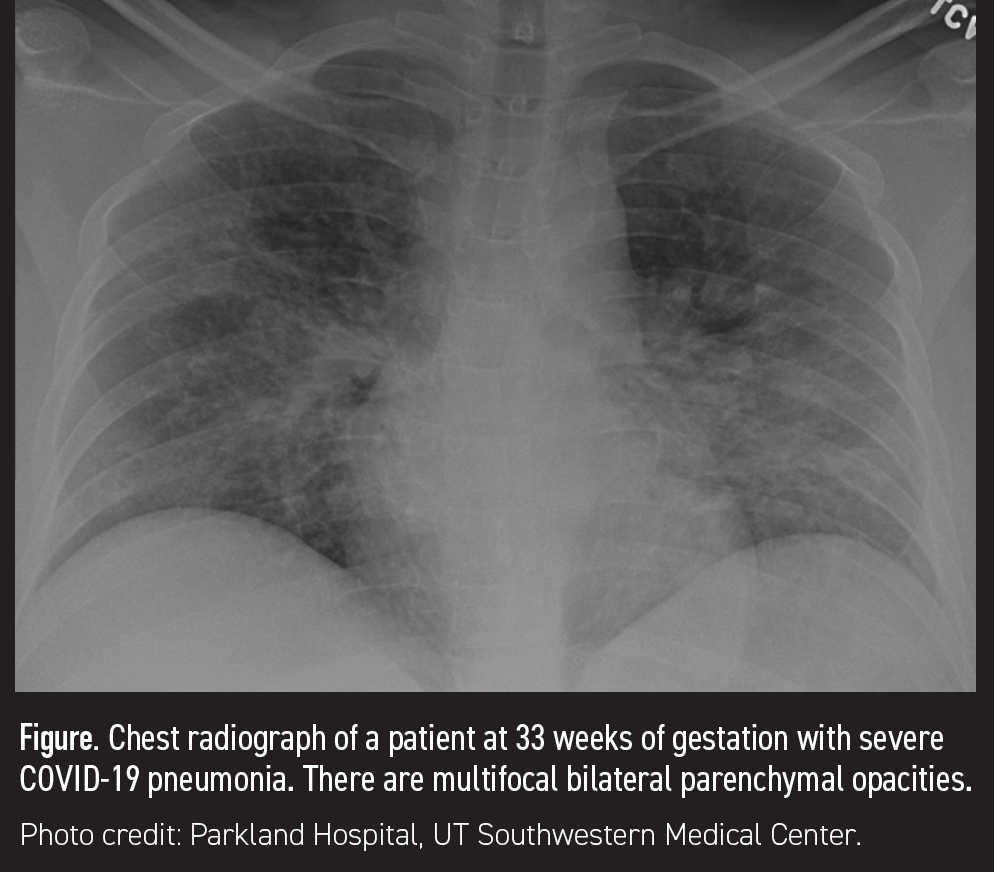

Figura. Radiografía de tórax de una paciente a las 33 semanas de gestación con neumonía grave por COVID-19. Hay opacidades parenquimatosas bilaterales multifocales.

Se debe realizar una radiografía de tórax en pacientes con enfermedad respiratoria de moderada a grave y repetirla si aumenta la necesidad de oxígeno para evaluar la extensión de la enfermedad pulmonar parenquimatosa. Las imágenes indicativas de neumonía viral de moderada a grave revelan opacidades en una distribución predominantemente periférica, con un patrón difuso demostrado en el SDRA temprano. Se debe considerar la angiografía pulmonar por TC (ATC) cuando persisten la hipoxia o la taquicardia a pesar de las opacidades mínimas demostradas en la radiografía de tórax o cuando la sospecha clínica de embolia pulmonar es alta. La ATC no está indicada de forma rutinaria para todas las pacientes embarazadas con COVID-19 y síntomas clásicos de disnea y tos cuando se demuestra enfermedad pulmonar parenquimatosa en la radiografía de tórax.